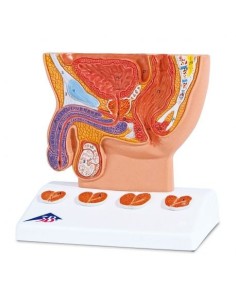

Dal cranio in 22 parti con incastri magnetici ai modelli di colonna vertebrale, da quelli di articolazioni a quelli di cuore, ogni pezzo della nostra collezione è progettato per un’immersione totale nello studio dell’anatomia umana. I nostri modelli, realizzati tramite scansioni di ossa vere, garantiscono un’esperienza tattile autentica e una fedeltà di peso quasi identica agli originali.

Essenziali per studenti e professionisti, i nostri modelli anatomici sono strumenti didattici che permettono di osservare le strutture anatomiche con precisione, eliminando la necessità di dissezioni o studi invasivi. Sono inoltre utili per spiegare ai pazienti le patologie, rendendo la comunicazione più efficace e risparmiando tempo prezioso.